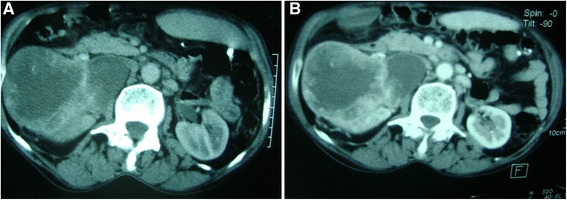

Figure 1.

Tomodensitometric scans reveal a mid-right renal tumor measuring 12cm. (A) The tumor is breaking the renal capsule. (B) Peripheral contrast-enhanced image.